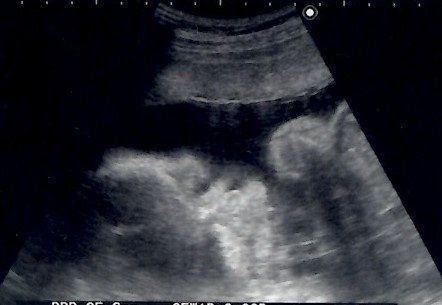

なつさんの妊娠30週目のエコー写真

どんな顔かわかるようになってきました

エコーで顔立ちがはっきり見られるようになりました。チェックしているときにしゃっくりをしていたのも見られました。恒例になっていたおしりチェックをしてもらうと、突然おしりの間に男の子のしるしが! 「今までの検診で何度も見ていたのに、どうして急にわかったんだろう」と家族と驚きました。